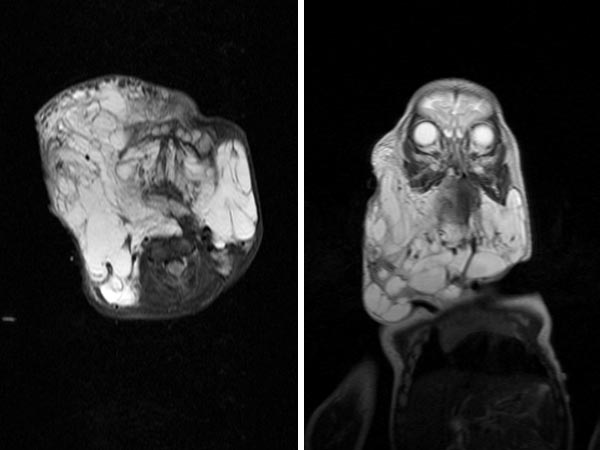

The course of treatment so far: from 2012 to 2013: two open surgical resections in the soft tissue in the submandibular region and first sclerotherapy treatment with OK-432. In 2014: renewed open resection of lymphatic malformation parts of the right cheek via facelift access with neuromonitoring of the facial nerve, combined sublingual resection, 2x sclerotherapy with OK-432. In 2015: CO2 laser resection of lymphatic malformation parts in the pharynx from intraorally. In 2016: closure of the tracheostoma, renewed sclerosing treatment with OK-432. In 2017: 3x sclerosing treatment with bleomycin (10 mg, 15 mg, 15 mg), the last time combined with OK-432. In 2018: last open resection in submental and submandibular region on the right side, thus soft tissue treatment now completed for the time being. The image shows the last MRI in January 2017.